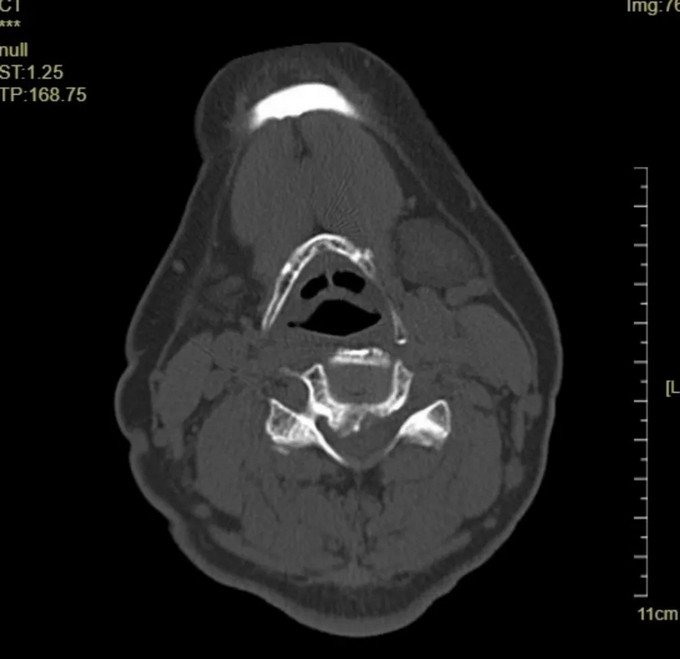

術前影像

頸椎CT橫斷位 可以看到明顯突出的骨贅